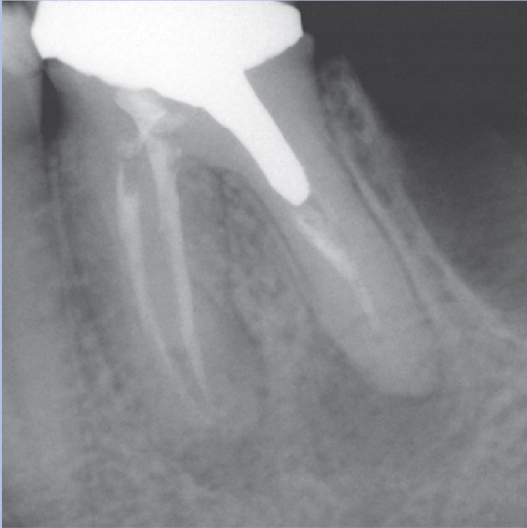

Before

After

Before Root Canal treatment

After Root Canal treatment